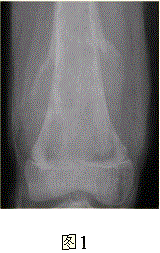

问题 患者男,16岁,左大腿下部疼痛伴肿胀2个月,逐渐加重。自感左膝上方胀痛,尤以夜间为著,伴行走困难。既往史及家族史无特殊。查体:左大腿下部明显肿胀,皮温较对侧升高。碱性磷酸酶明显增高。股骨平片及MRI见下图。 应该首先考虑的诊断为

选项 A.急性化脓性骨髓炎 B.骨结核 C.骨肉瘤 D.畸形性骨炎 E.骨转移瘤 F.软骨肉瘤

答案 C